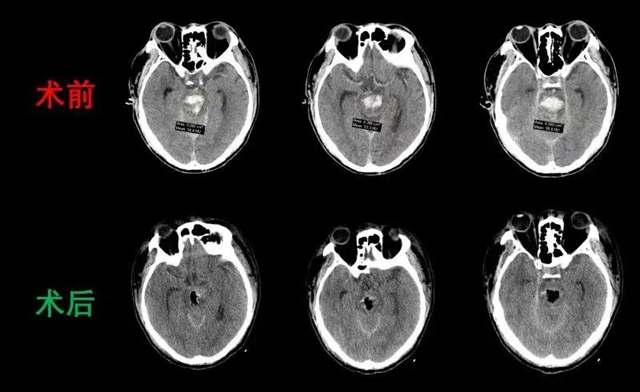

急诊行脑CT提示王先生为脑干出血,神经外科立即组织多位医生联合会诊,制定出手术方案。在王先生入院仅半小时后,便对其实施了高精度脑干出血微创手术,完成这个手术的团队包括,手术团队:明扬教授、周杰教授、李昊、李慎杰、何海平等医生,麻醉:唐健文,手术护士:吴倩,唐小燕,整个团队经过四小时鏖战,最终将王先生从鬼门关拉了回来。

当脑干出血超过5ml(约1个手指的大小)就需要手术治疗,对于脑干出血的有效救治目前仍是医学难题。“王先生脑干出血量高达到15ml(约3个手指的大小),因此手术精度和难度相当高”。

术后即刻患者双侧瞳孔缩小,一侧缩小较为明显,说明出血对脑干的压迫得到了有效的缓解,术后颅脑CT提示脑干的血清除满意。